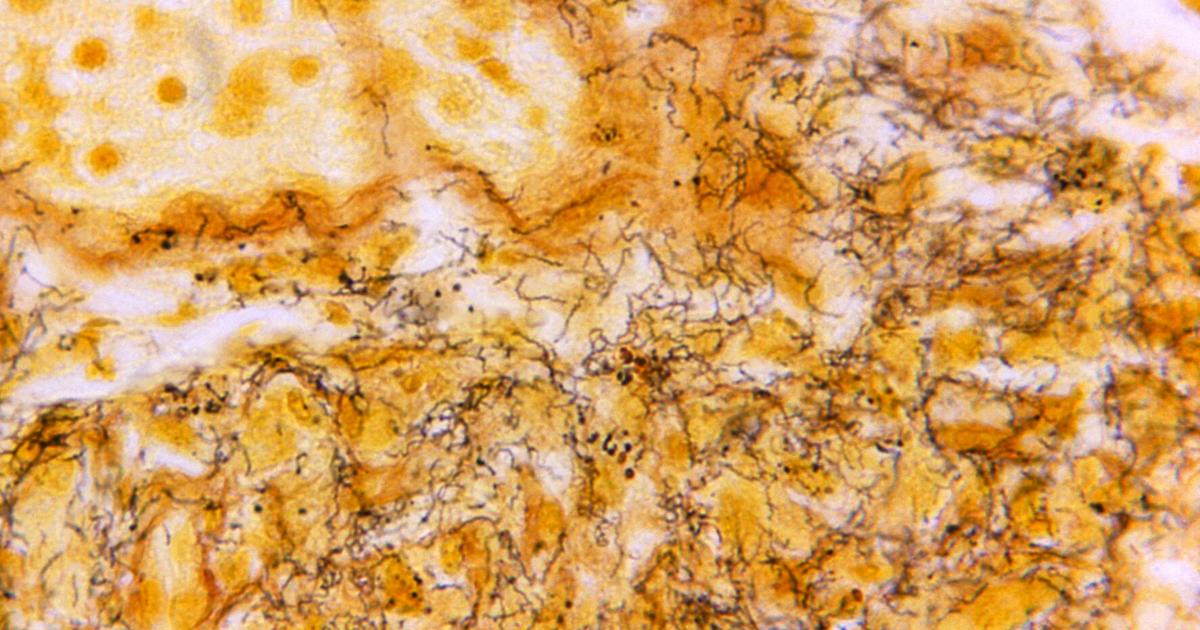

Syphilis is a bacterial disease that surfaces as genital sores but can ultimately lead to severe symptoms and death if left untreated.